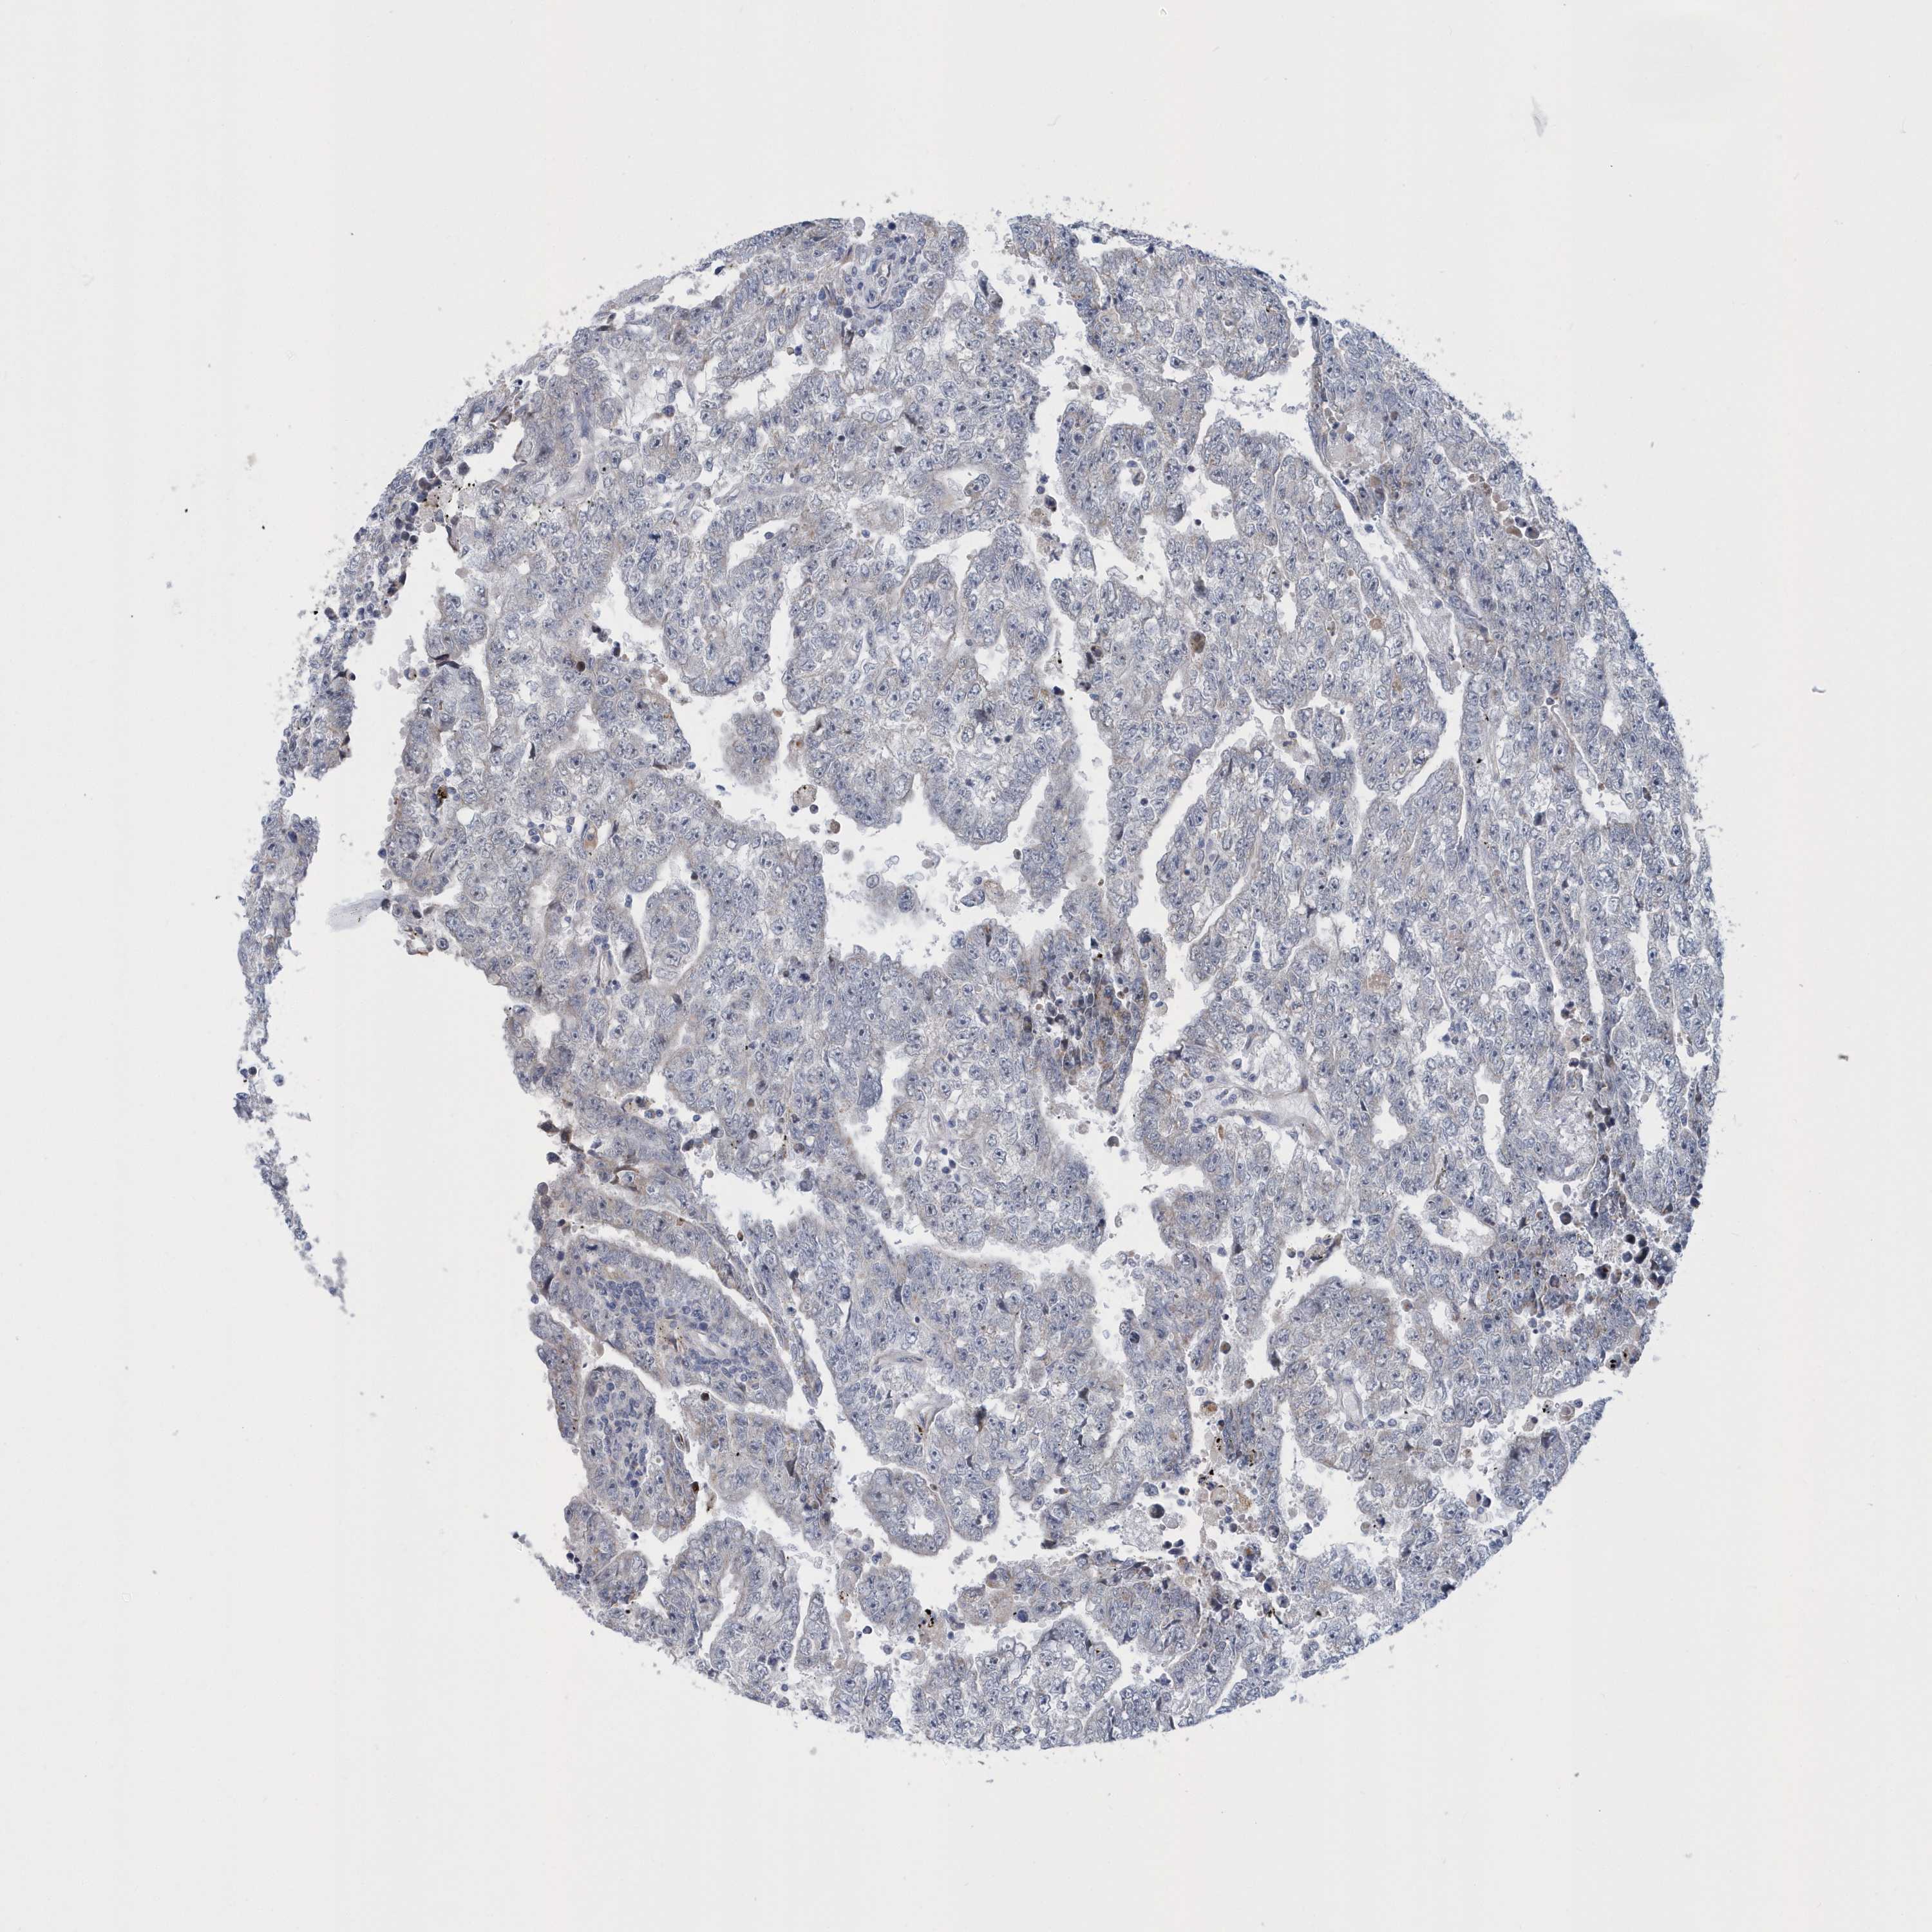

TESTIS CANCER - Protein expressioni

A mouse-over function shows sample information and annotation data. Click on an image to view it in a full screen mode. Samples can be filtered based on level of antibody staining by selecting one or several of the following categories: high, medium, low and not detected. The assay and annotation is described here.

Note that samples used for immunohistochemistry by the Human Protein Atlas do not correspond to samples in the TCGA dataset.

Antibody stainingi

Antibody staining in the annotated cell types in the current human tissue is reported as not detected, low, medium, or high, based on conventional immunohistochemistry profiling in selected tissues. This score is based on the combination of the staining intensity and fraction of stained cells.

Each image is clickable and will lead to virtual microscopy that enables deeper exploration of all samples and also displays staining intensity scores, fraction scores and subcellular localization as well as patient and tissue information for each sample.

Antibody HPA036823

Antibody HPA036824

Antibody HPA061412

Carcinoma, Embryonal, NOS